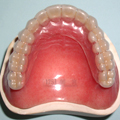

対症療法というのは、不快な症状を軽くすることに主眼をおいた治療で、具体的には関節や筋肉の痛みに対して鎮痛剤や筋弛緩剤(筋肉をやわらげる薬)を内服したり、薄い材質のマウスピースをはめて関節をガードしたりします。